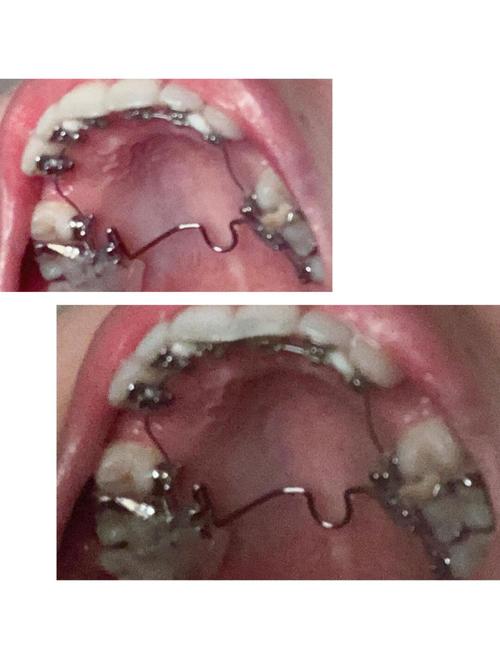

粘接与初始加力

托槽到货后,医生在口内分区域粘接(通常分上下颌两次,每次1-2小时),使用特殊粘接剂确保托槽稳固,粘接后立即放置初始弓丝,开始轻力移动牙齿,此时患者可能出现轻微酸胀、异物感,1周左右可适应。